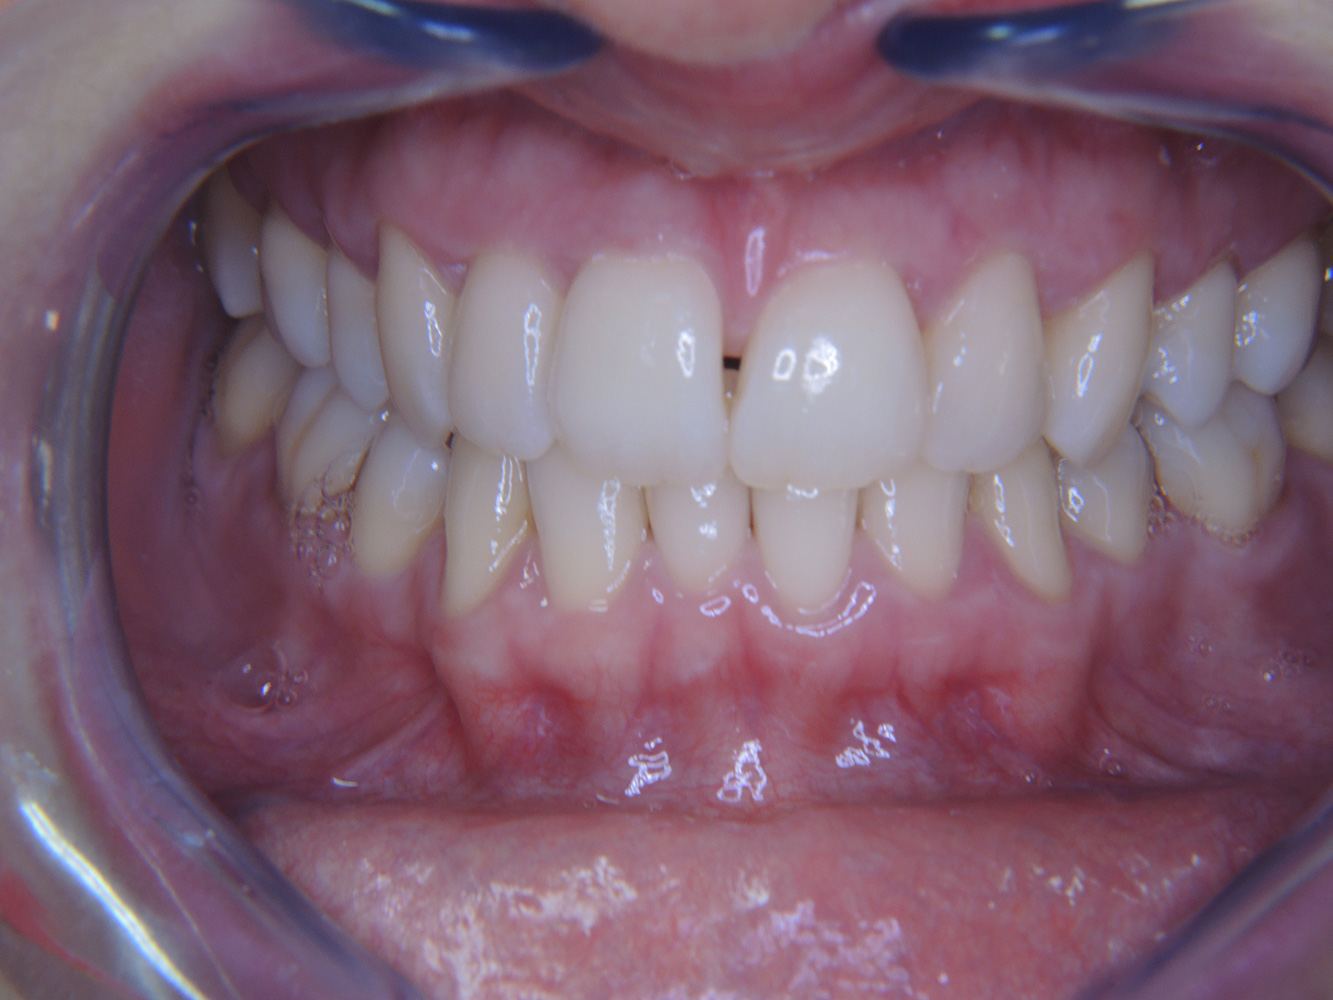

Pacient diabetic cu o bună sănătate

O pacientă diabetică de 51 de ani, cu o bună sănătate orală, se prezintă pentru o ședință de profilaxie. Glicemia este stabilă la HbA1c = 6.2%, prin urmare, se consideră că starea ei este suficient de bine gestionată cu medicamentul antidiabetic metformin. Pacienta nu prezintă lucrări dentare sau patologie orală. Cu ajutorul rezultatelor dentare, este posibilă determinarea gingivitei în ciuda condițiilor de altfel stabile. mai multe